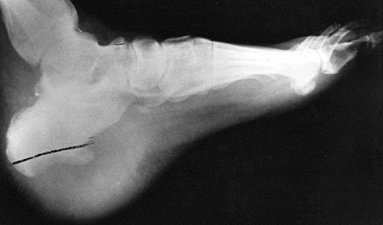

reported to be the most common organism causing infection following

nail puncture wounds of the foot. The treatment that produces the best

results consists of surgical drainage, debridement, and curettage of

the puncture wound in the bone, and debridement of all necrotic bone,

along with specific antibiotic therapy. The antibiotic of choice for Pseudomonas

infections is generally tobramycin, in combination with either

piperacillin or a third-generation cephalosporin, depending on the

sensitivity reports. Continue systemic antibodies for approximately 3

weeks (Fig. 133.17, Fig. 133.18).

![]() |

Figure 133.18.

Anteroposterior radiograph of a 6-year-old child shows osteomyelitic changes of the proximal metaphysis with involvement of the first metatarsal phalangeal joint. |